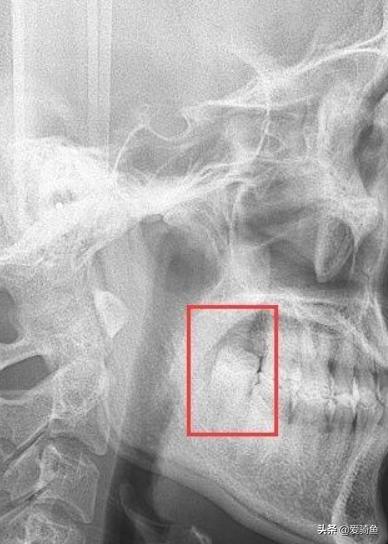

下颚俩垂直阻生智齿